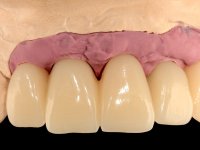

O paciente foi observado conjuntamente e a dúvida que surgiu de imediato foi se seria possível com a regeneração óssea a efectuar poder ser reabilitada naturalmente a zona das papilas interdentárias. Nesse sentido foi feito um enceramento de diagnóstico que contemplaria as duas hipóteses, utilizando ou não a cerâmica gengival. A confecção desse enceramento foi fundamental para expor ao paciente a dificuldade da reabilitação. O wax-up deu origem a um mock-up que foi aprovado pelo paciente e que simultaneamente serviu de guia imagiológica. O caso foi planificado cirurgicamente e realizada uma guia cirúrgica com que foram colocados os implantes. Após 10 semanas foi feita a 1ª impressão para confecção da ponte provisória. Foram criados os primeiros perfis de emergência na gengiva artificial e foi digitalizado o modelo. Por processo de CAD-CAM foi confeccionada uma ponte provisória aparafusada baseada no enceramento de diagnóstico. A ponte trabalhou durante 8 semanas os tecidos moles que foram fielmente copiados numa impressão com técnica de moldeira aberta. Os transferes foram individualizados com resina composta para copiarem fielmente os perfis de emergência criados pela ponte provisória. Confeccionado o modelo de trabalho definitivo, foi realizada uma infra-estrutura em zircónio seguindo a orientação do enceramento de diagnóstico. O assentamento da infra-estrutura foi testado em boca e simultaneamente foi novamente impressionados os tecidos moles com um silicone fluido. Nessa consulta foi feito o levantamento da cor. Os dentes 13 e 23 apresentavam uma saturação anormalmente forte que resolvemos não valorizar, optando por privilegiar a relação com o sector antero-inferior. Foi realizada uma nova gengiva artificial com a impressão que acompanhou a impressão de arrasto com a infra-estrutura. Após a colocação da cerâmica na infra-estrutura foram coladas as meso-estruturas. O trabalho final foi aparafusado lentamente permitindo a adaptação dos tecidos moles.